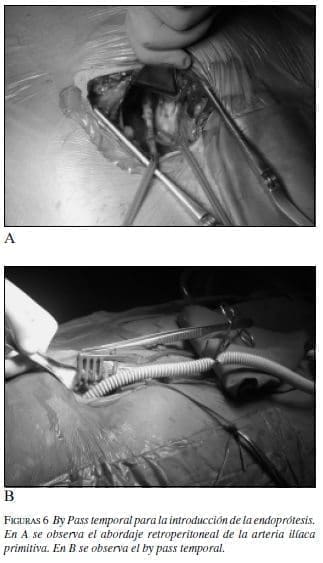

Si la gran cantidad de calcio o el pequeño diámetro en toda su longitud impiden el avanzar el transportador, se puede realizar un by pass temporal a la arteria ilíaca, dejando un extremo libre que permita pasar la endoprótesis.

El ángulo ilíaco es el más agudo en el trayecto entre la femoral común y la bifurcación aórtica. Se cuantifica en una escala de 0 a 3 que combina el índice de tortuosidad y el ángulo más agudo, la angulación máxima recomendada en las ilíacas es de 90 grados (12, 20) (figura 6).